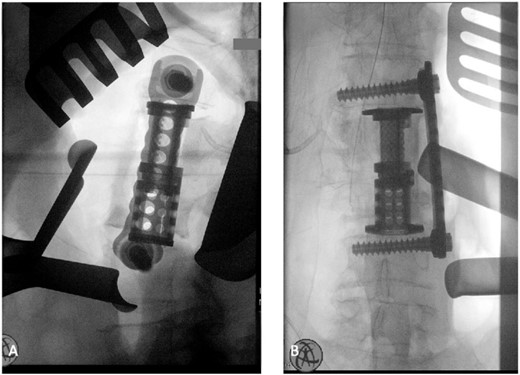

The patient was placed in the operating room for anterior lumbar interbody fusion via thoracoabdominal (TA) incision for retroperitoneal exposure. The patient was placed in the right-lateral decubitus position. The 10th rib interspace was identified, and a curvilinear incision was made from the midaxillary line and extended anteriorly and inferiorly toward the umbilicus. The retroperitoneal plane was entered, and the 11th rib was cut and morcellated for lumbar cage placement. The diaphragm was divided radially with electrocautery to further expose the abdominal cavity and retroperitoneal space. The lateral border of the psoas muscle was exposed and dissected into the anterior vertebrae L1–L4. The aorta and abdominal viscera were retracted toward the patient’s right side using an Omni retractor. Copious necrotic tissue and caseating granulomas were removed. The L2–L3 vertebrae were exposed, corpectomy was performed, and a titanium cage was placed with a plate spanning from L1 to L4 (Fig. 2A and B). To achieve added stability, a second surgery for posterior percutaneous screw placement without lumbar fusion was performed (Fig. 3). The patient recovered without complications and was subsequently discharged to a skilled nursing facility, and ultimately home. At the 1-month follow-up visit, the patient’s TA incision had completely healed, and there was no evidence of recurrent infection.

Intraoperative fluoroscopy depicting two pedicle screws posteriorly placed in a percutaneous fashion with a 5.5 × 100 mm2 rod placed in the pedicle tulips.